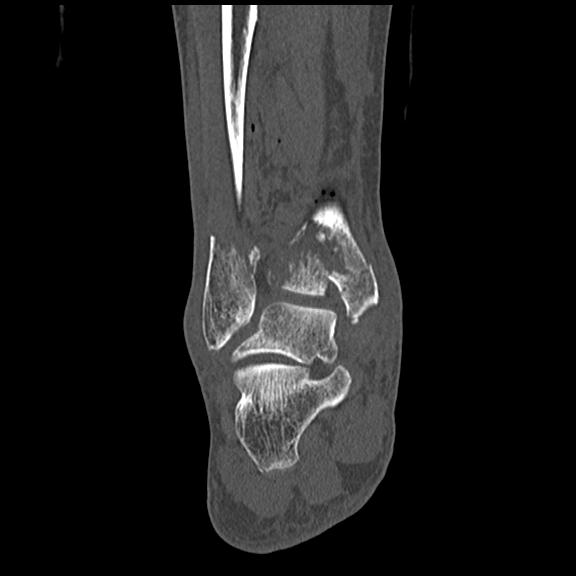

102755 1/4 2R 1/15 2R 右足関節 68歳女性 右三果脱臼骨折